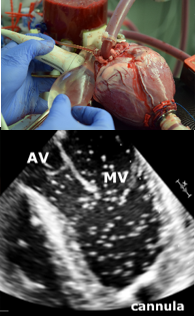

Strömungsvisualisierung (Echo-PIV) mit Ultraschall-Techniken

Die Herzechokardiographie ist die wichtigste bildgebende Routineuntersuchung bei PatientInnen mit Herzinsuffizienz und wird auch zur Beurteilung der Leistungsfähigkeit von Herzklappen und Herzmuskelgewebe eingesetzt. Ihre Zuverlässigkeit ist jedoch manchmal nicht bewiesen, insbesondere bei neuen Geräten. Im Versuchsaufbau kann die Leistung neuer Geräte oder Technologien (z.B. Herzklappen, Anastomosentechniken) anhand standardisierter experimenteller Messungen (Particle Image Velocimetry - PIV) getestet und bewertet werden.